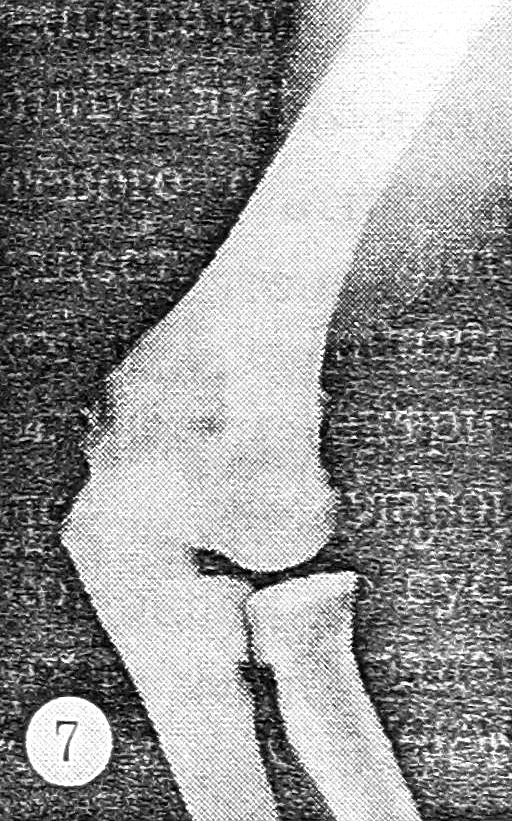

III | Боли в суставе после нагрузки | Предплечье пассивно отводится на 20°, атрофия мышц плеча (3 см) и предплечья (1,5 см) | Ширина внутреннего отдела суставной щели в больном суставе в 3 раза больше, чем в здоровом (рис. 7) | Нарушение герметичности полости сустава по его внутренней и передней поверхности (рис. 8) | 5 |

Рис. 7. Рентгенограмма левого локтевого сустава, выполненная в специальной укладке: нестабильность III степени.